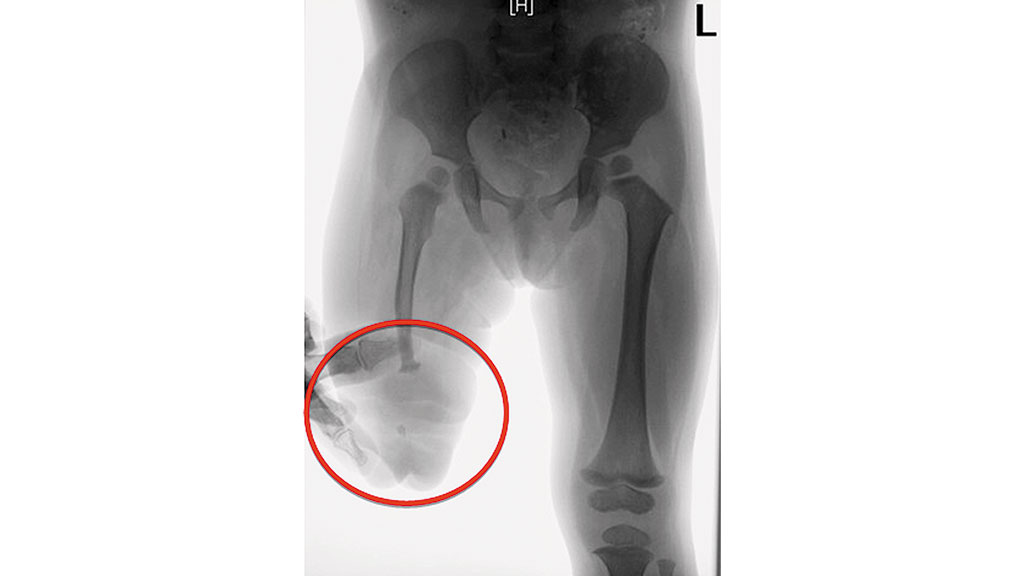

Mit fünf Jahren fusionierte man die einzelnen distalen Knochensegmente mit einer Schraube, die man nach einem halben Jahr entfernte (Abb. 13). Seither wird die Patientin mit längsovalen Schäften (M.A.S.) versorgt (Abb. 14). Die dafür verwendeten Fuß- und Kniepassteile brachte die Patientin in kürzester Zeit mit Defekten zurück, besonders die Vierachskniegelenke mit Federvorbringer. Bei der derzeitigen Versorgung nutzten die Orthopädie-Techniker ein einachsiges Kniegelenk mit Hydraulik und den Pediatric-Prothesenfuß (Abb. 15).